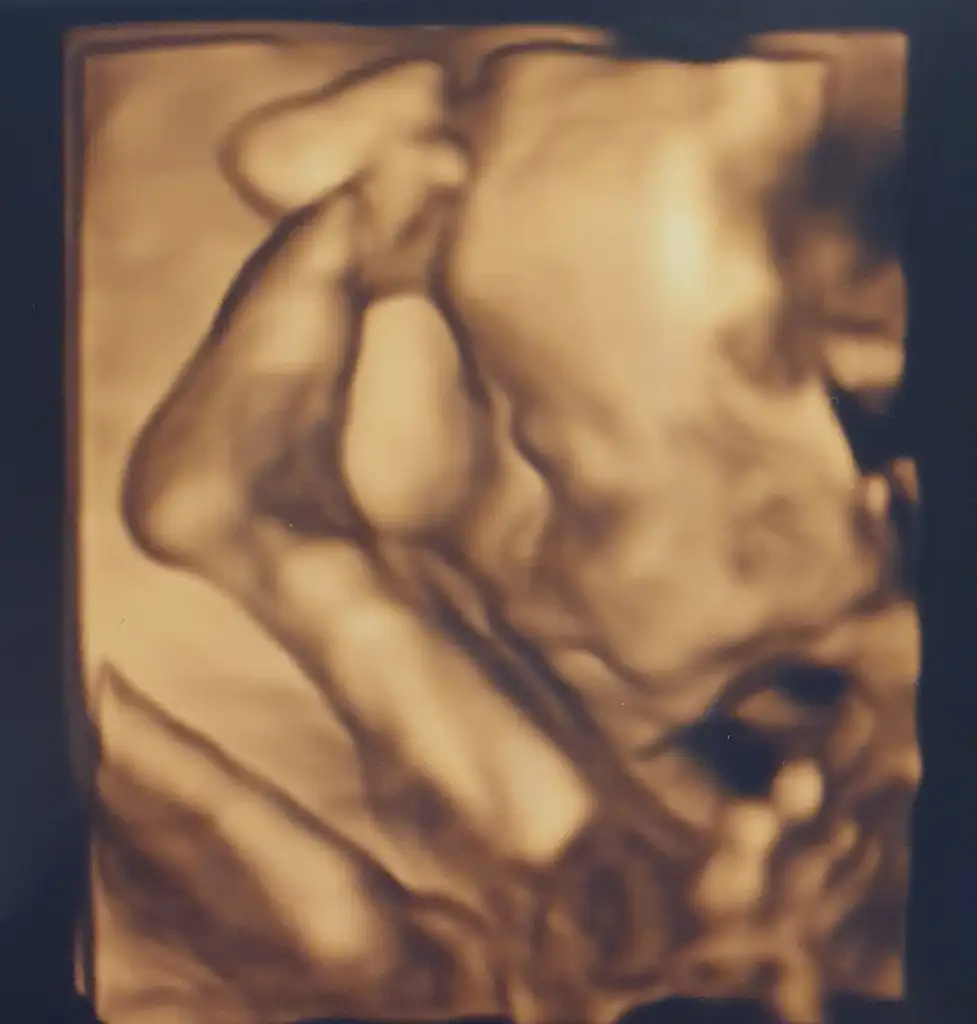

Ayy maşallah yaAa foto eklemeyi unutmuşum kızlarr

Bu da benim fındık kurdum

Ayaklarını kafasının üstünde eliyle tutuyordu

Ayy maşallah ya

Artık nasıl net görünüyorlar

senin kuzuş bayağı akrobatik maşallah ne güzel poz vermiş öyle

Aa foto eklemeyi unutmuşum kızlarr